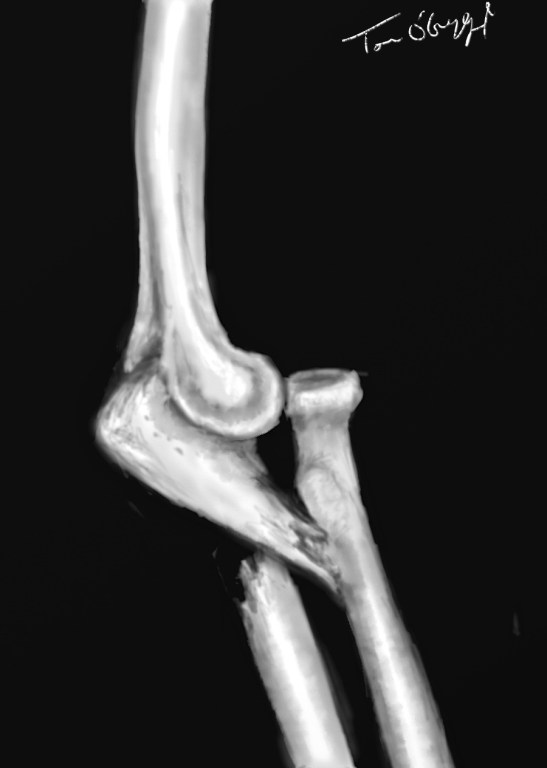

fracture de Monteggia : fracture de l’extrémité supérieure de l’ulna et luxation de la tête radiale

Fracture de Monteggia

Elle associe une fracture de l’ulna à la jonction tiers supérieur tiers moyen et une luxation de la tête radiale à l’articulation radio-cubitale supérieure.

Le déplacement peut se faire dans le type 1 tête radiale vers l’avant, fragment ulnaire supérieur pointant vers l’avant. Le type 2 montre un déplacement postérieur conjugué de la tête radiale et du fragment ulnaire supérieur. Le type 3 montre un déplacement latéral de la tête radiale et du fragment ulnaire supérieur. Le type 4 montre un déplacement antérieur de la tête radiale et il existe à la fois une fracture de l’ulna et du tiers supérieur du radius.